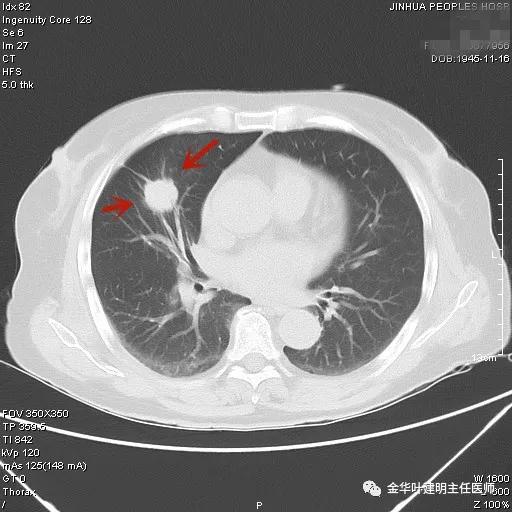

上图示浸润性腺癌典型表现。实性结节,有细毛刺征,有血管进入病灶,部分地方有浅分叶。